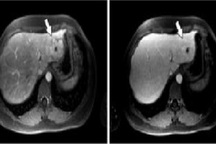

Nam thanh niên mới đây được gia đình đưa đến Bệnh viện Đa khoa Hùng Vương (Phú Thọ) khám. Bác sĩ chỉ định chụp CT - scanner đa dãy ổ bụng để chẩn đoán chính xác bệnh.

Kết quả gan có hình ảnh khối có tính chất ác tính, xơ gan, lách to, giãn tĩnh mạch vành vị, giãn đường mật gan trái.